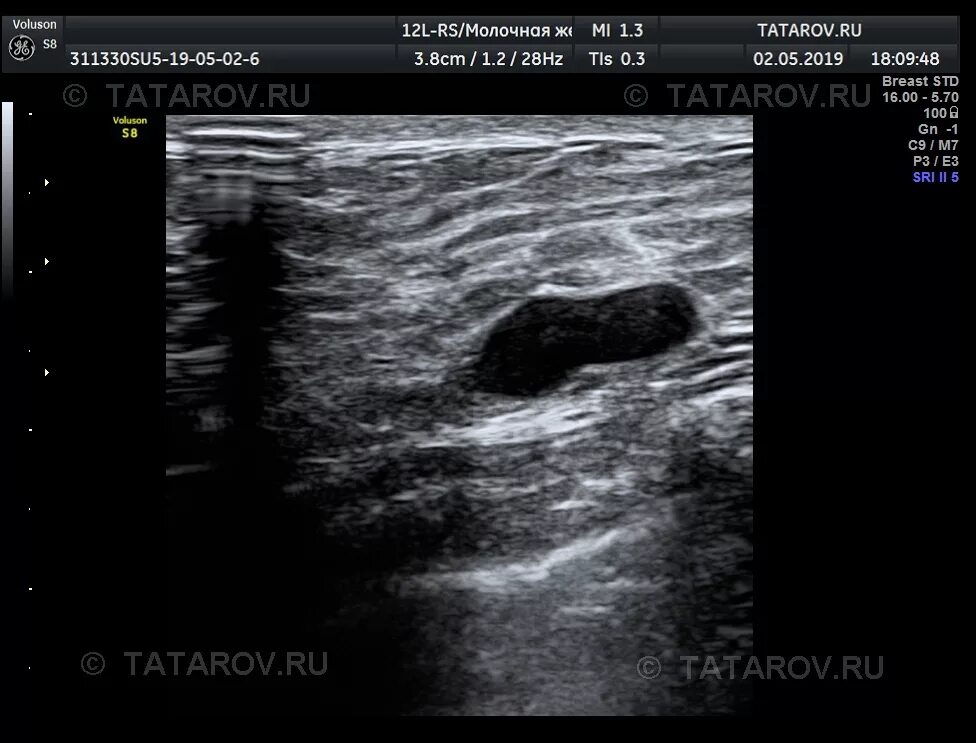

Узи молочных киров